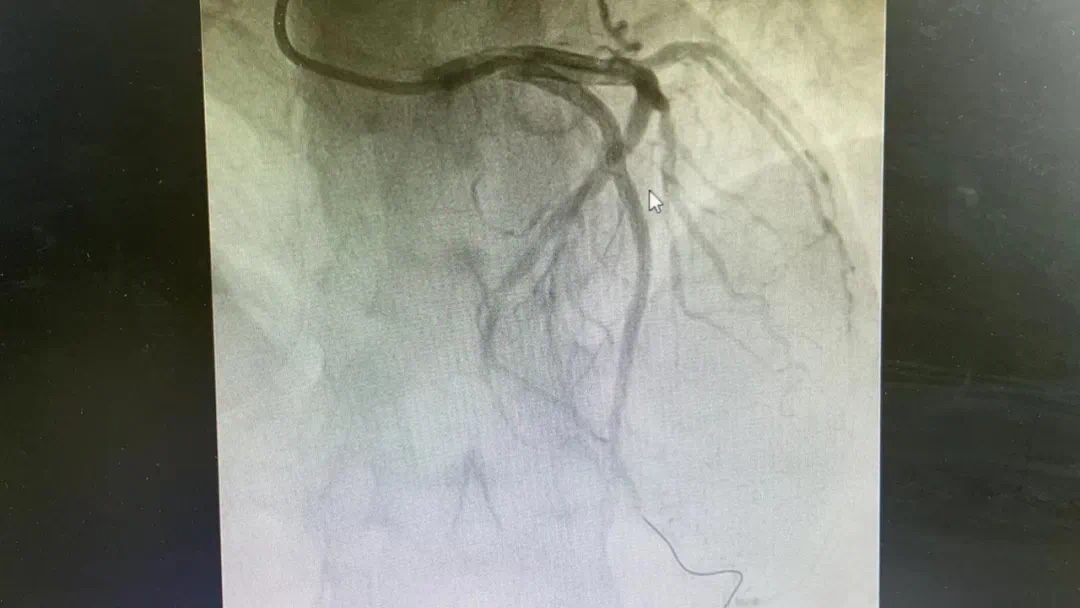

副主任何涛、医师熊俊锋、护士张梅梅顾不上休息,立刻投入到第三次抢救中。胸痛中心团队心内科与急诊科无缝衔接,23点26分在导管室开通堵塞血管,又成功救治一名急性心肌梗死患者。患者张某送至导管室施行急诊冠脉介入治疗,经过快速的术前准备,以mini Crush术式于回旋支远段植入波科冠脉支架一枚,再于钝缘支中段至回旋支中段植入Firebird2冠脉支架一枚。患者症状大幅缓解。零点42分手术结束,复查患者血压、心率正常后将患者送回病房。

术前、术后图片如下